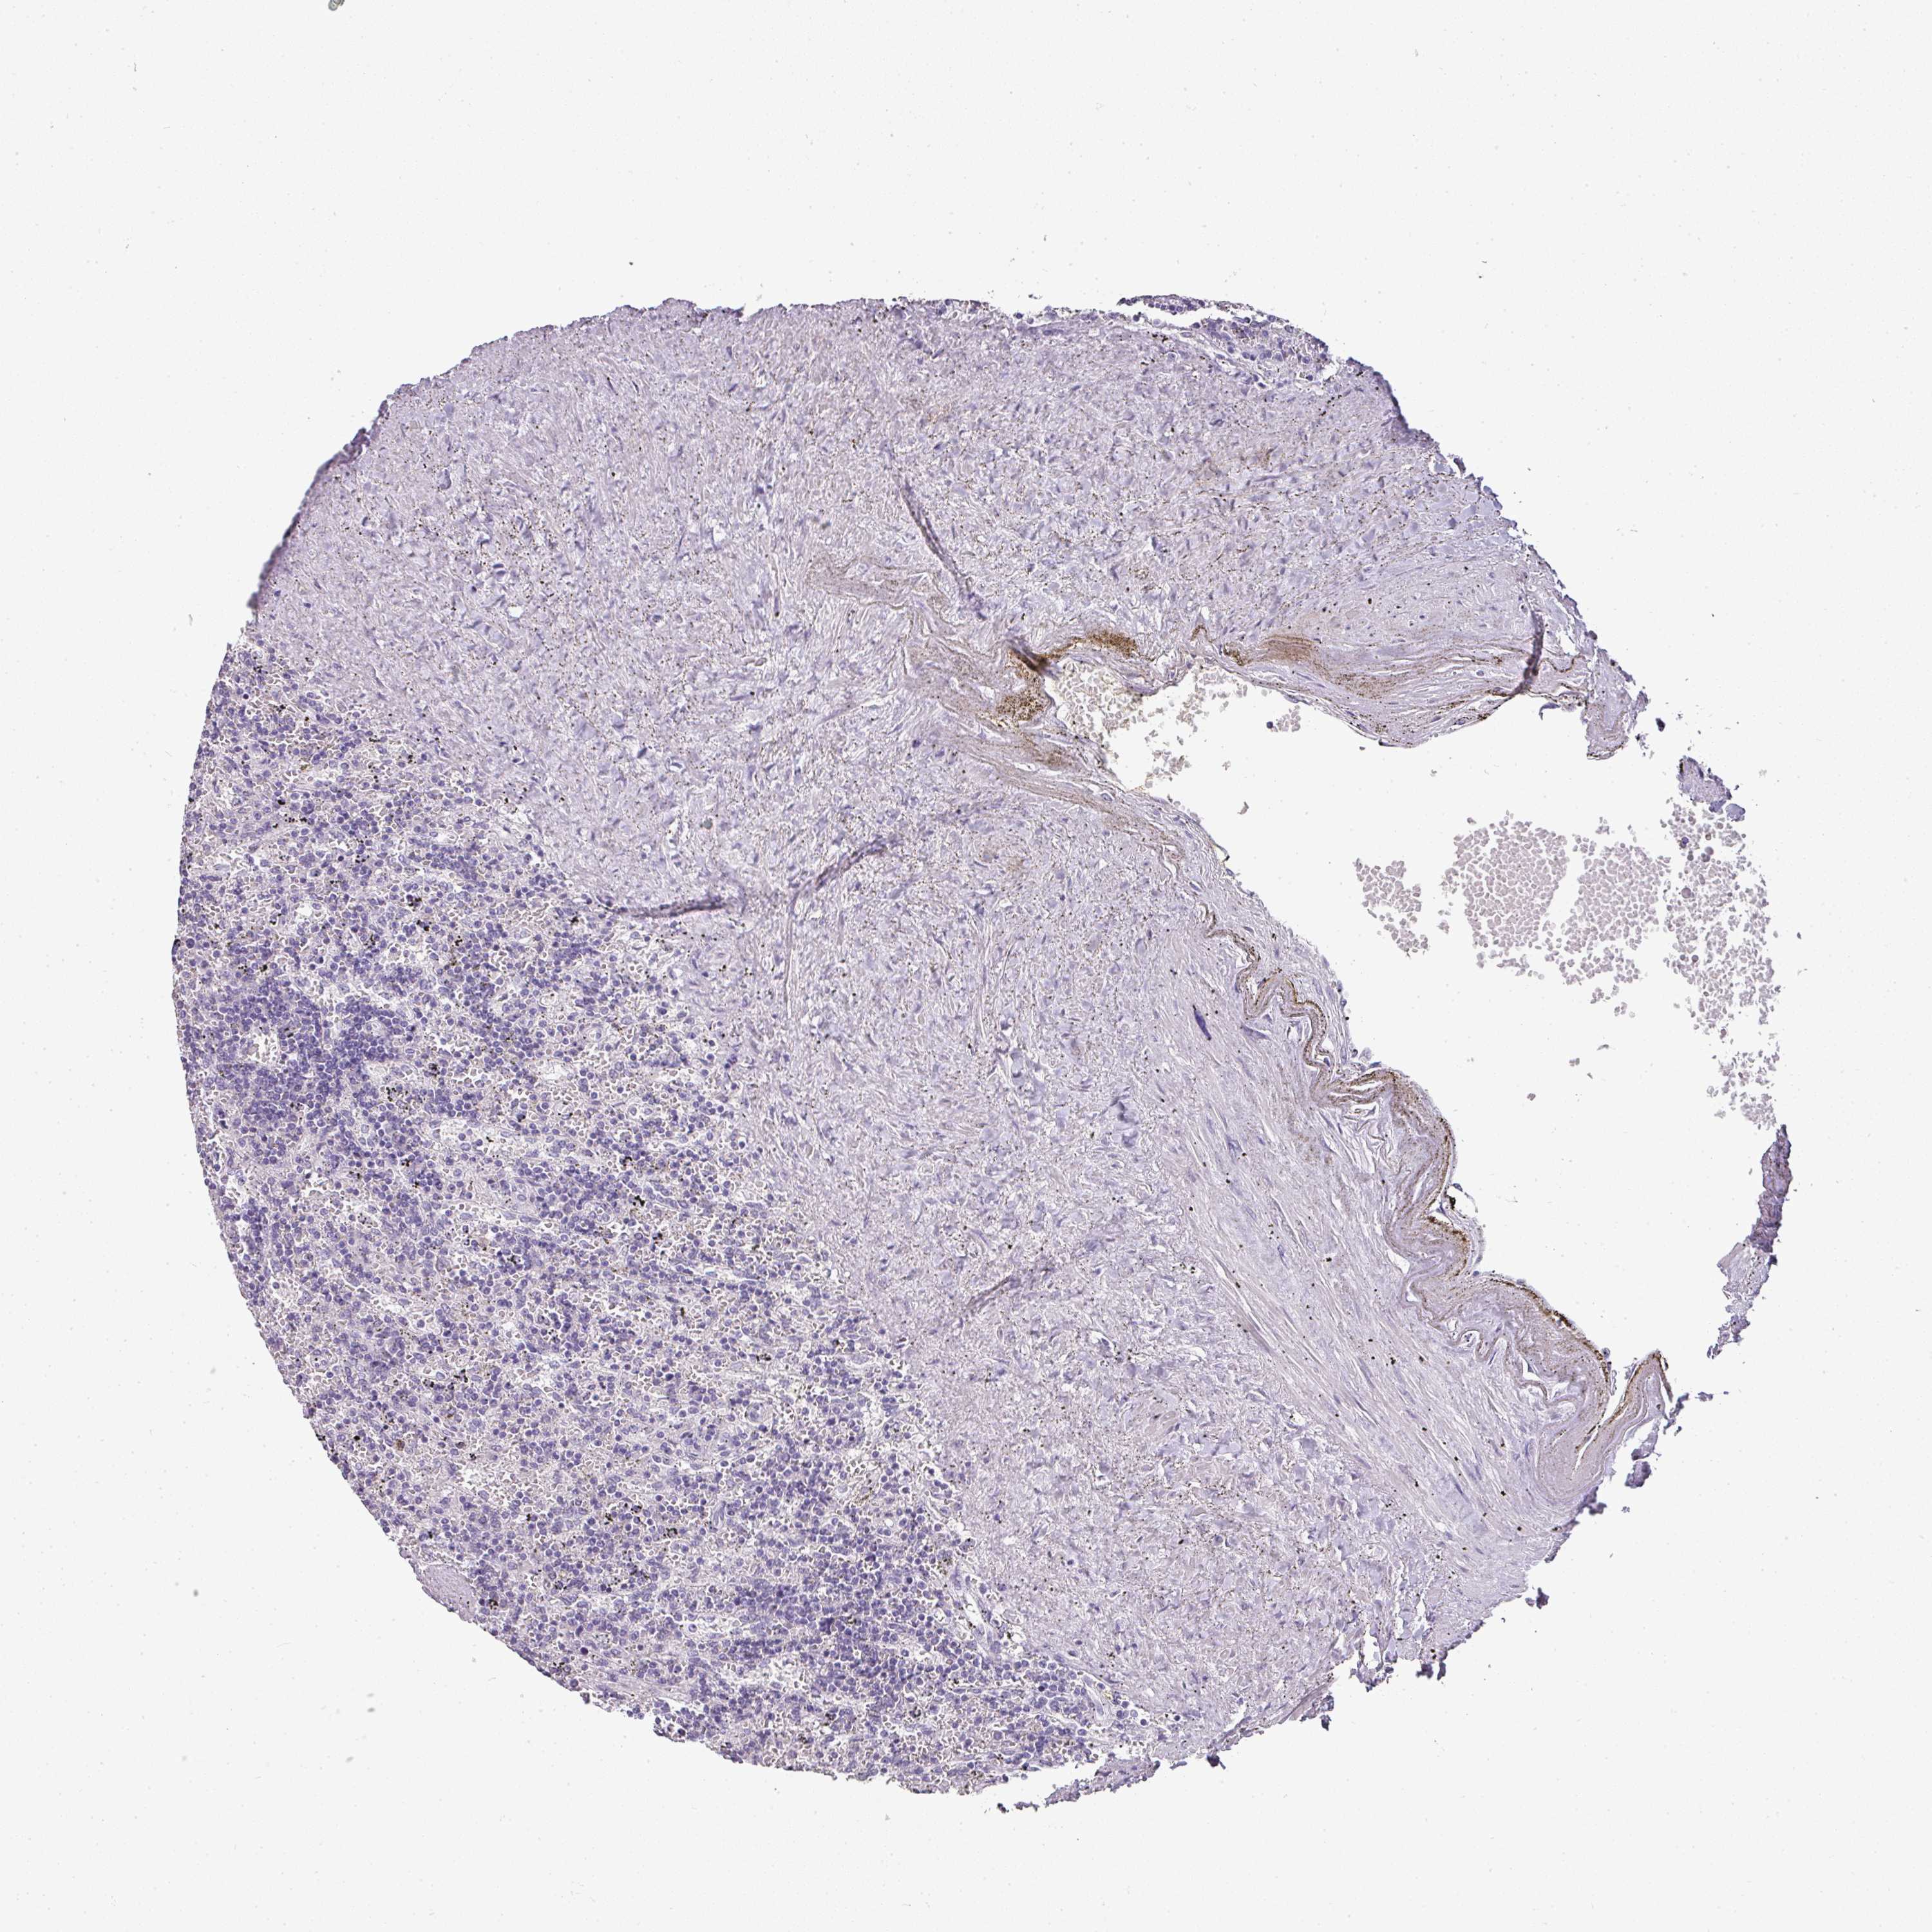

LYMPHOMA - Protein expressioni

A mouse-over function shows sample information and annotation data. Click on an image to view it in a full screen mode. Samples can be filtered based on level of antibody staining by selecting one or several of the following categories: high, medium, low and not detected. The assay and annotation is described here.

Each image is clickable and will lead to virtual microscopy that enables deeper exploration of all samples and also displays staining intensity scores, fraction scores and subcellular localization as well as patient and tissue information for each sample.

Antibody CAB016522

Hodgkin's disease, NOS

Malignant lymphoma, non-Hodgkin's type, High grade

Malignant lymphoma, non-Hodgkin's type, Low grade